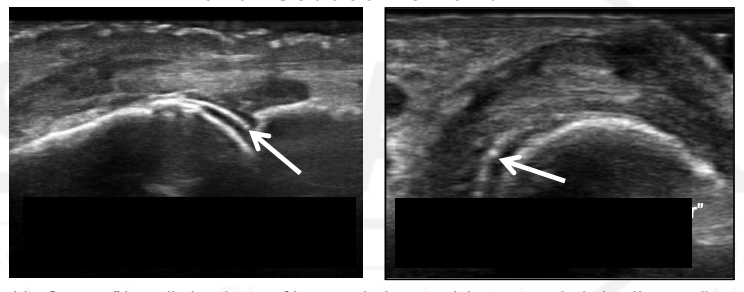

What view is this?

PIP

Synovium

Extensor Tendon

Proximal Phalanx

Middle Phalanx